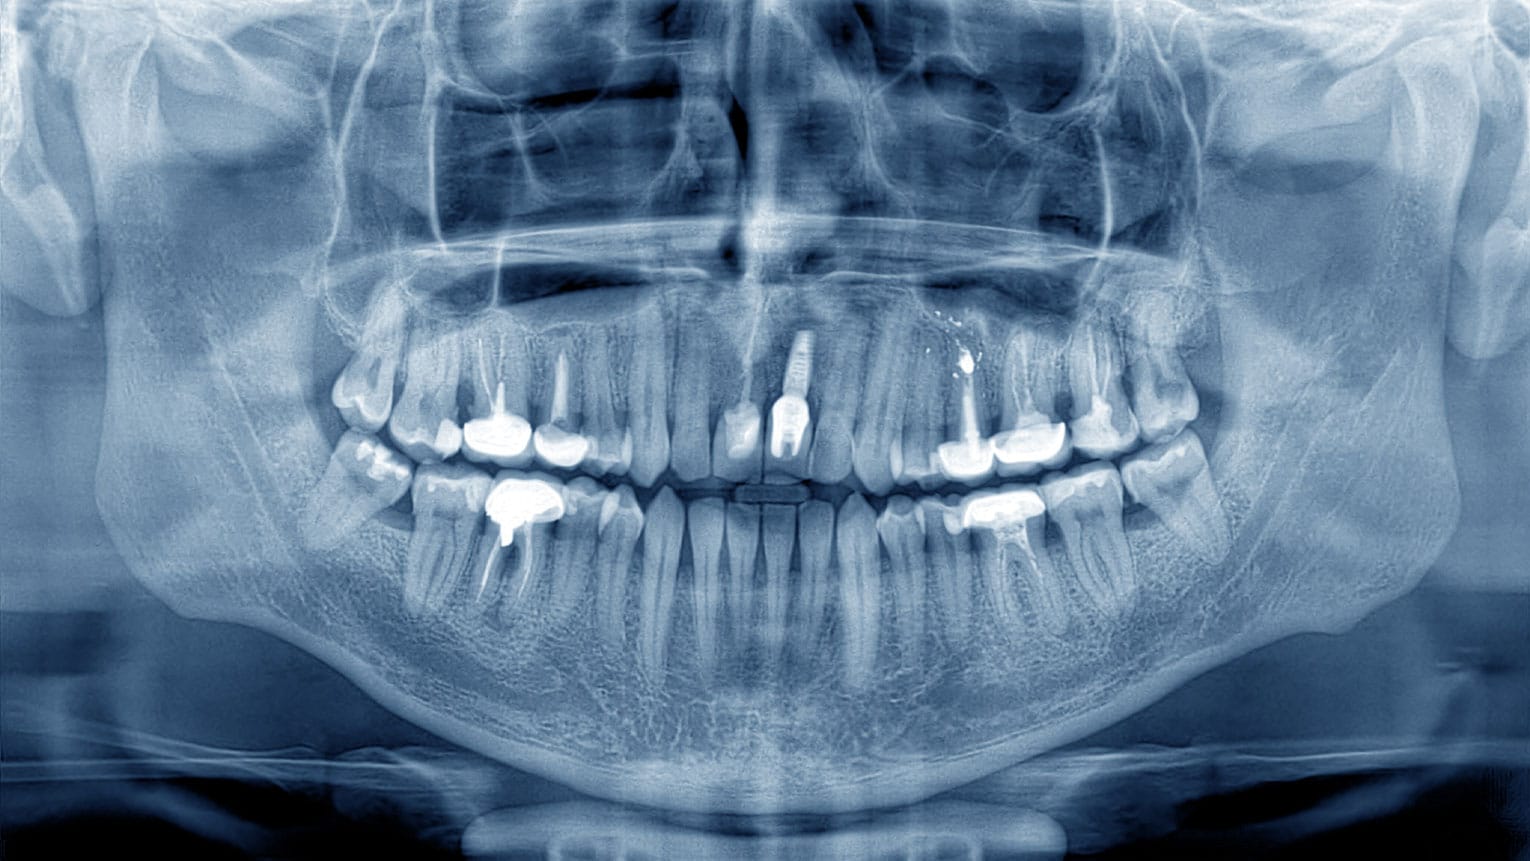

3 min read Dental Implants

Dental Implant Steps Explained

Dental implants are the only permanent solution for missing teeth and are fast becoming the gold standard tooth replacement option. 6% of Americans have implants, and by 2026 that number is set to grow to 23% due to the aging population of…